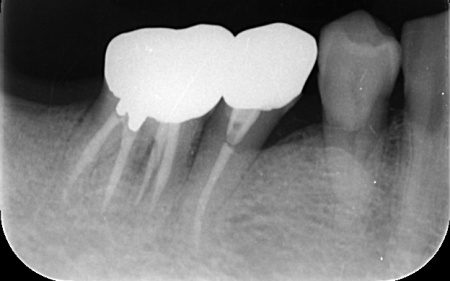

| カウンセリング | 拝見したところ、右下奥歯2本が噛むと痛む状態でした。 これらの歯は、以前神経を除去する処置を行っており、その後銀歯にされていたとのことです。 詳しく調べるためにレントゲン撮影を行った結果、どちらの歯も歯根が割れていることが確認できました。 歯根が割れた歯は元の状態に戻すことができず、そのまま放置すると炎症が広がって周囲の骨や隣接する歯に悪影響を及ぼすリスクがあります。 以上のことから、抜歯をしたうえで歯を補う治療が必要だと診断しました。 |